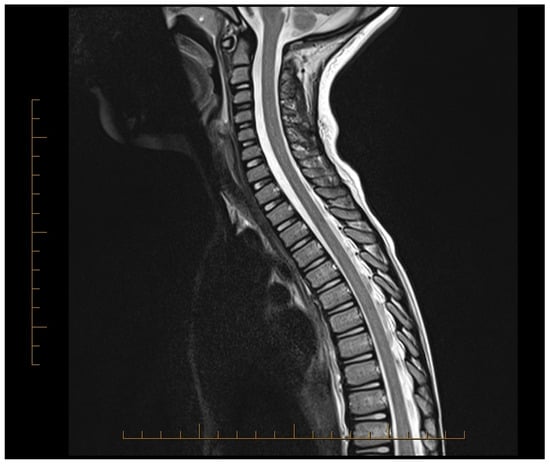

| 2017 | Hsu [27] | CR | Taipei, Taiwan | 1 | 12 | M | Sudden onset low back pain followed by quadriplegia, hyperalgesia, flaccid bladder, and altered consciousness. MRI showed diffuse T2 hyperintensity from cervical cord to conus medullaris. | MP TPE | After TPE, limb function improved, bladder/rectal issues resolved. At 6 months: independent eating, supported ambulation, EDSS 5 |